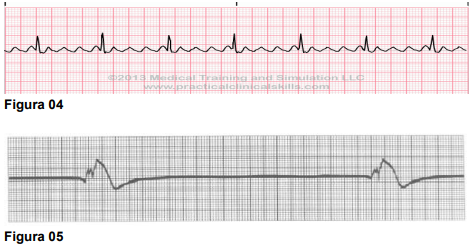

A seguir, apresentam-se cinco traçados cardíacos que devem ser analisados quanto à sua morfologia e frequência, a fim de identificar corretamente o tipo de arritmia associado a cada um, respectivamente.

Assinale a opção CORRETA, referente à sequência das arritmias apresentadas: